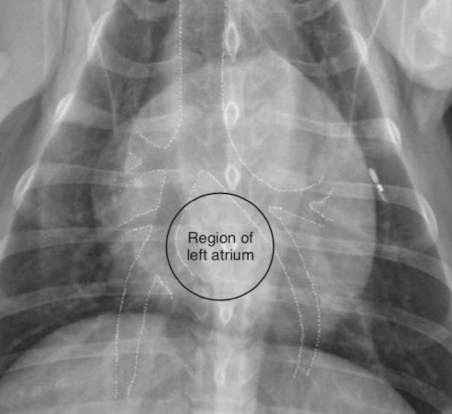

Where is the left atrium seen on vd?

What is the arrow pointing to?

Left atrial enlargement (increase opacity)